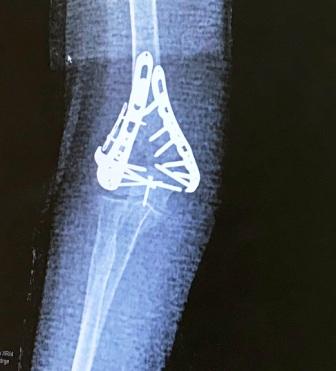

...just before Barbara broke her elbow while walking Charlie in Yuba City.

One unexpected pull put her and her elbow down on a neighbor's lawn.

A collision with the bender board in the flower bed broke her elbow.

The doctors at UC Davis did a great job repairing a nasty break.